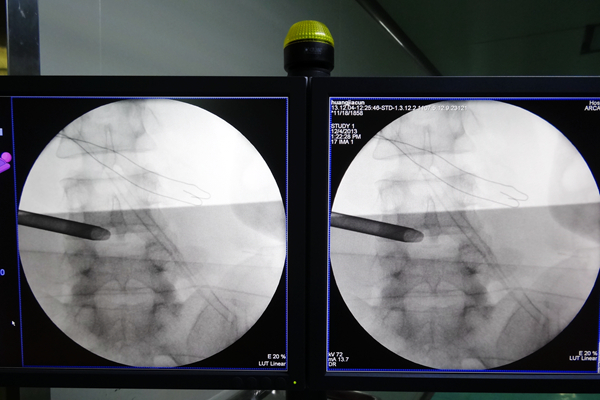

手术中

手术过程展示